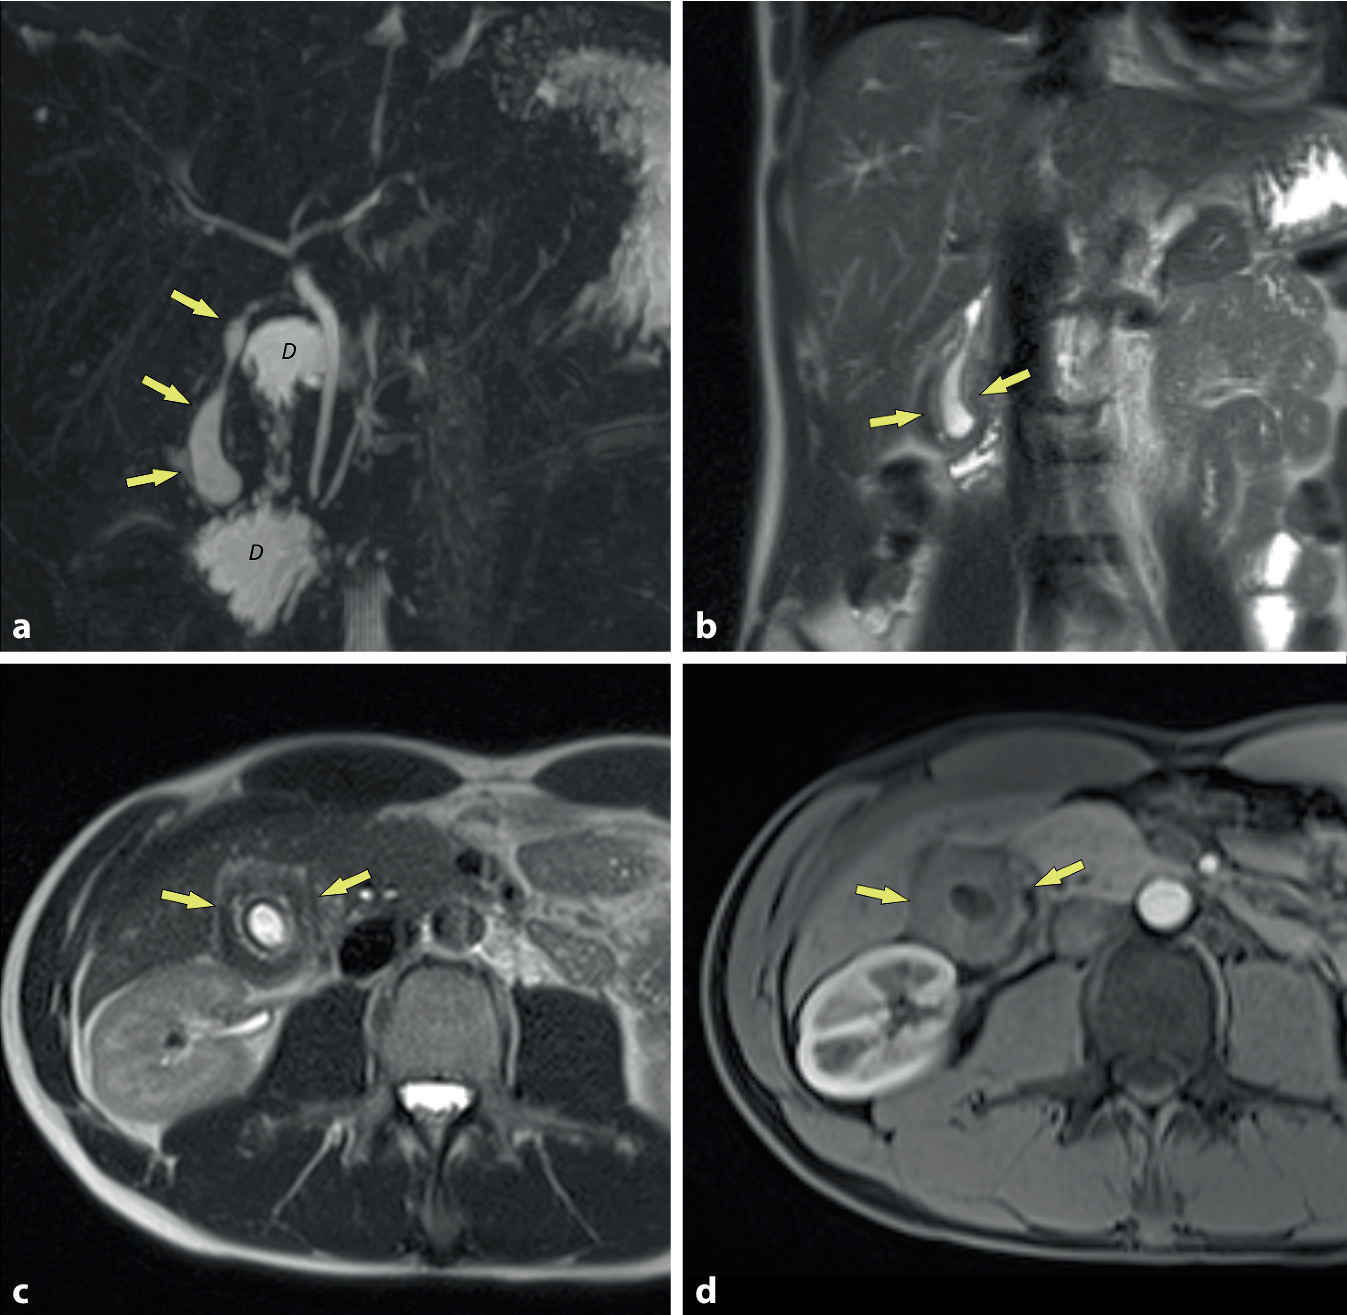

Ein 33-jähriger Patient, der seit 1 Jahr immer wieder unter postprandialem Unwohlsein und Druckgefühl im rechten Oberbauch litt, wurde an unsere Institution überwiesen. Die Beschwerden hatten in den letzten 6 Monaten vor der Aufnahme deutlich zugenommen und waren mittlerweile praktisch nach jeder Mahlzeit vorhanden. Eine auswärts durchgeführte Oberbauchsonographie zeigte eine stark verdickte Gallenblasenwand (max. 1 cm), jedoch ohne Hinweis auf das Vorliegen entzündlicher Veränderungen oder Steine. Im auswärts durchgeführten Labor zeigten sich unauffällige Leberfunktionsparameter und kein Hinweis auf das Vorliegen einer Entzündung. Der Patient brachte Bilder einer auswärts durchgeführten Magnetresonanzcholangiopankreatikographie (MRCP) mit. Diese zeigte eine diffuse Wandverdickung der Gallenblase mit geringem Volumen, jedoch keine entzündlichen Veränderungen. Vor allem war aber keine Lithiasis nachweisbar (Abb. 1).

Die koronale Magnetresonanzcholangiopankreatikographie (MRCP; a) zeigt das geringe Volumen der Gallenblase (Pfeile; D Flüssigkeit im Duodenum). Die koronale (b) und die axiale T2-gewichtete MRT(Magnetresonanztomographie)-Sequenz (c) zeigen anschaulich die zirkuläre, gleichmäßige Wandverdickung der Gallenblase mit sehr geringem Volumen. Gallensteine oder ein entzündliches Ödem des umgebenden Fettgewebes sind nicht nachweisbar. Die kontrastmittelverstärkte MRT (d) zeigt nur geringes Enhancement der Gallenblasenwand, was für einen Tumor oder eine Cholezystitis ungewöhnlich wäre